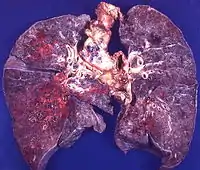

Кандидозна пневмонія

Вона рідко розвивається окремо і пов'язана з генералізованим кандидозом у рідкісних випадках. Найбільш частим ураження при цьому є абсцеси легень внаслідок гематогенного поширення видів Candida. Хворі скаржаться на задишку, кашель, гарячку. Фізикальне обстеження виявляє дихальну недостатність, розсіяні різного калібру хрипи.